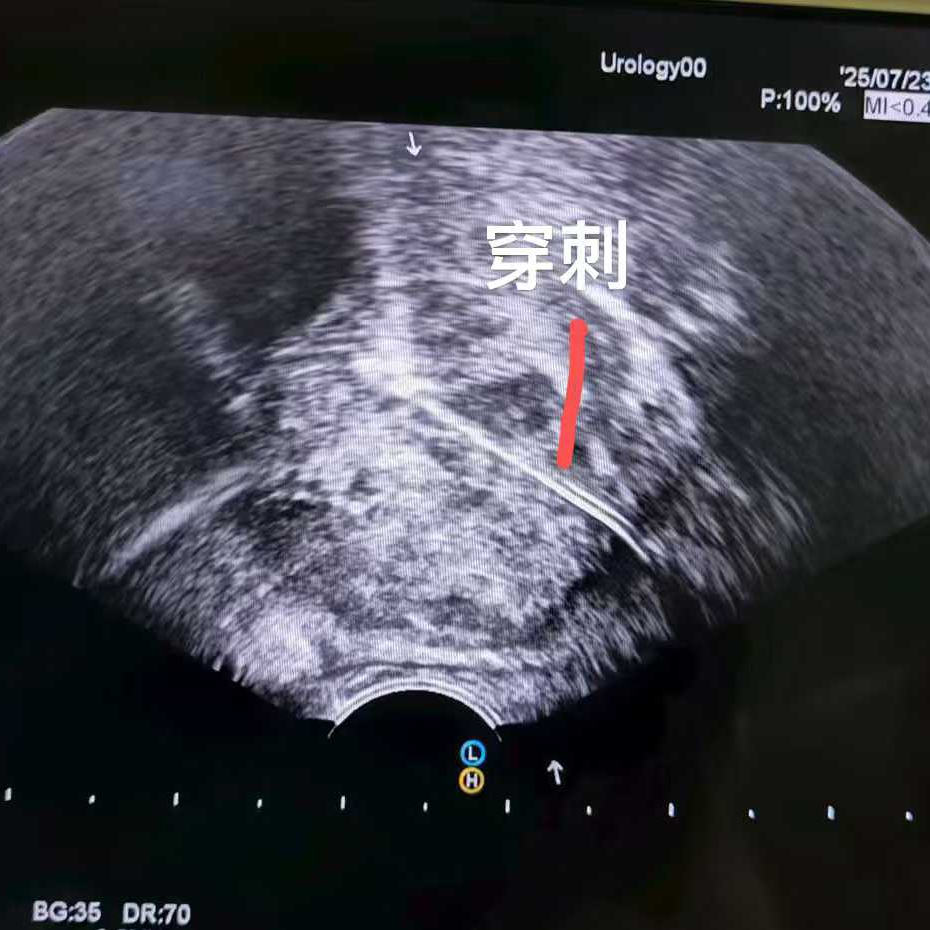

比如這位馬來西亞患者,PSA指標正常,但影像卻發(fā)現(xiàn)可疑病灶,結(jié)果穿刺證實是少見的前列腺尿路上皮癌,在我院接受了冷凍消融治療。